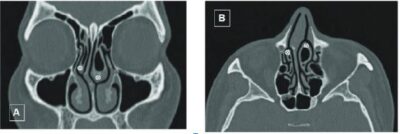

Source: ResearchGate